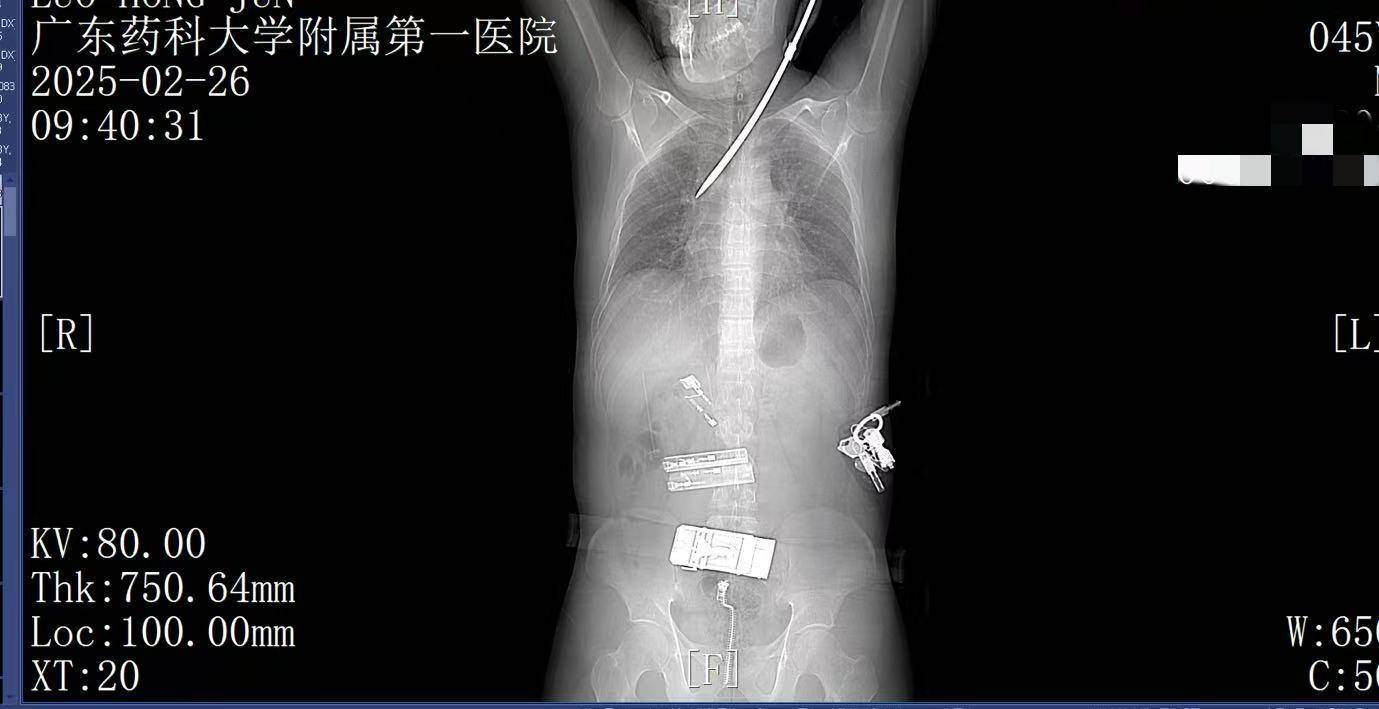

9:41,快速完成头+胸+腹部CT检查,经多学科会诊,明确螺丝刀异物刺入肺部btc地址。CT显示螺丝刀紧贴肋间血管、上肺后段动脉,尖端距右肺门仅2厘米,一旦贸然拔出螺丝刀,极有可能引发大出血,导致失血性休克甚至死亡,必须紧急手术。

9:39,救护车到达医院大门,院内急救团队已经做好准备btc地址。在紧密监护的情况下,全程采用绿色通道。到达医院时,罗师傅已经面色苍白,呼吸急促。螺丝刀已深深刺入罗师傅右肺,随时可能因大出血而危及生命。